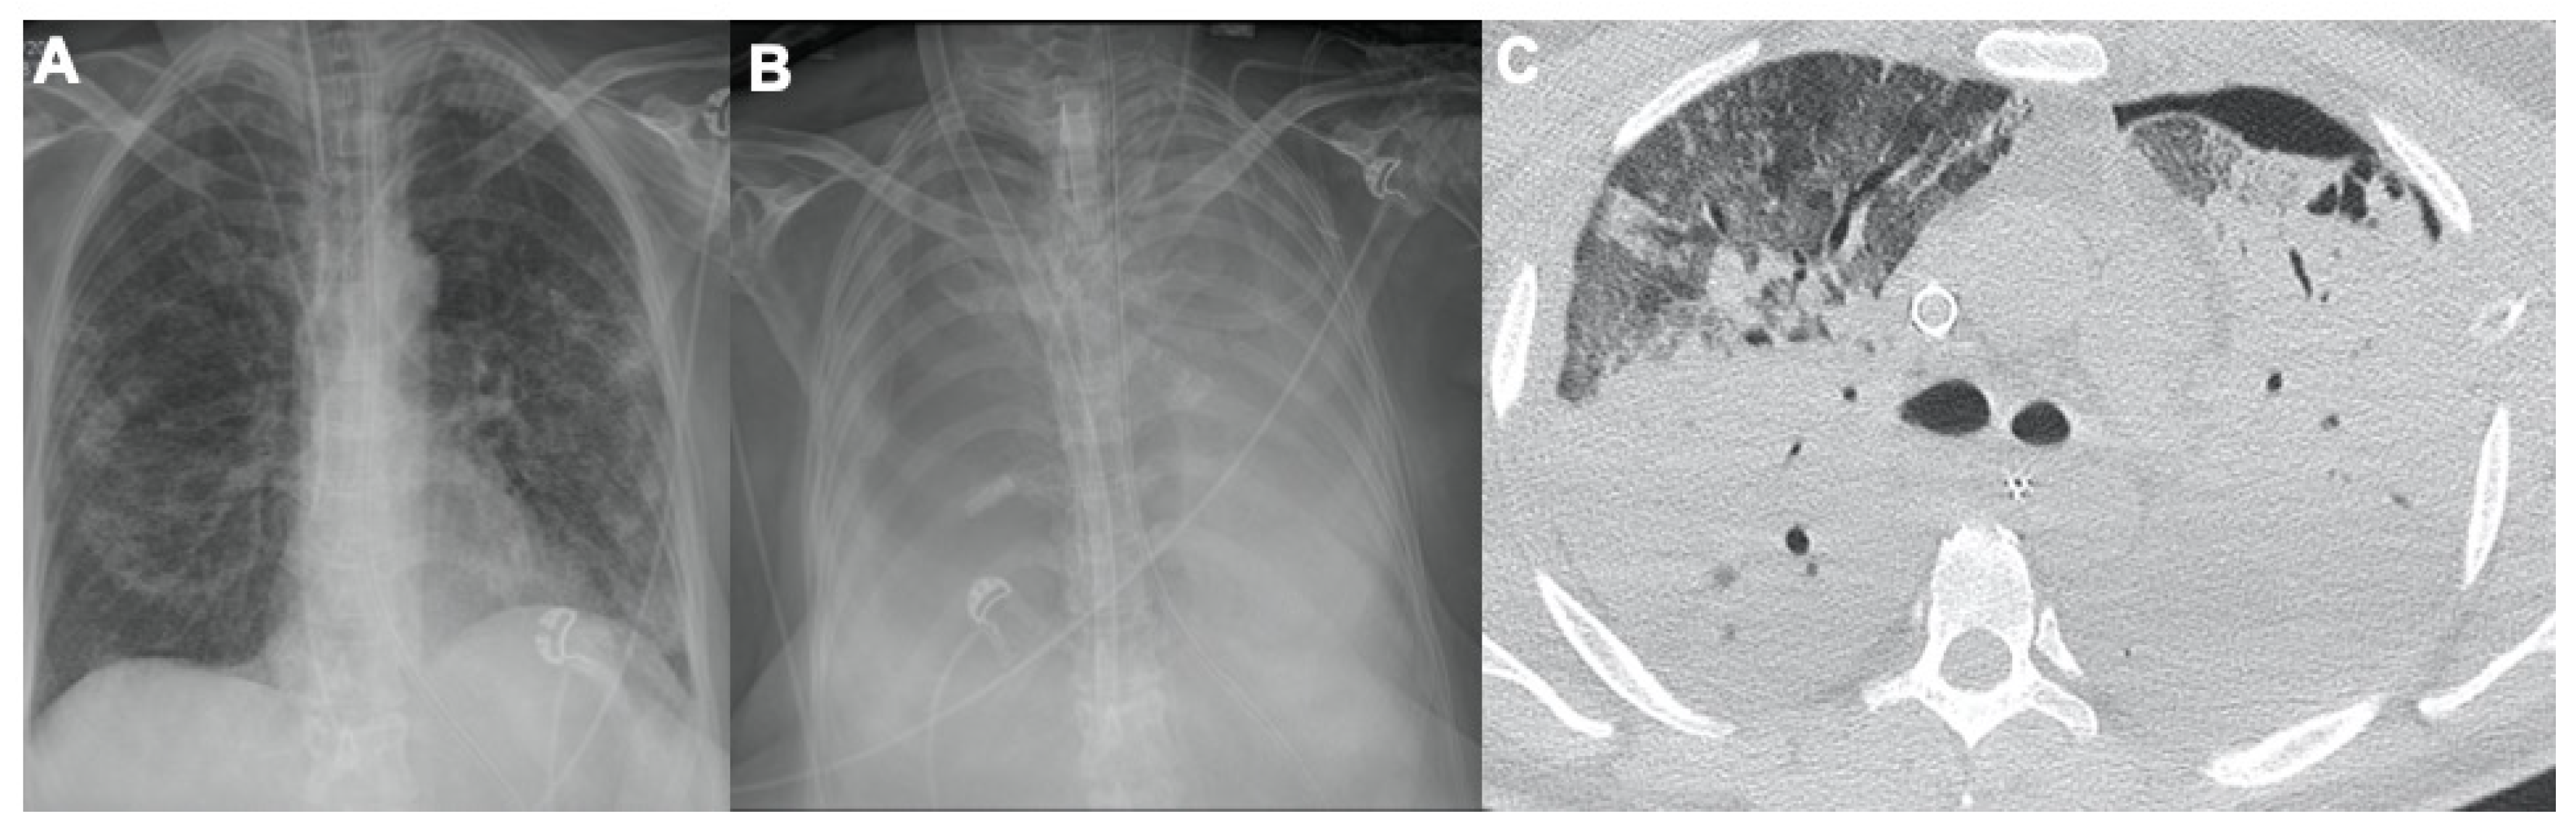

2.3. Pulmonary Embolism

- Ippolito, D.; Giandola, T.; Maino, C.; Pecorelli, A.; Capodaglio, C.; Ragusi, M.; Porta, M.; Gandola, D.; Masetto, A.; Drago, S.; et al. Acute pulmonary embolism in hospitalized patients with SARS-CoV-2-related pneumonia: Multicentric experience from Italian endemic area. Radiol. Med. 2021, 126, 669–678. [Google Scholar] [CrossRef]

- Grillet, F.; Behr, J.; Calame, P.; Aubry, S.; Delabrousse, E. Acute Pulmonary Embolism Associated with COVID-19 Pneumonia Detected with Pulmonary CT Angiography. Radiology 2020, 296, E186–E188. [Google Scholar] [CrossRef] [PubMed] [Green Version]

- Masselli, G.; Almberger, M.; Tortora, A.; Capoccia, L.; Dolciami, M.; D’Aprile, M.R.; Valentini, C.; Avventurieri, G.; Bracci, S.; Ricci, P. Role of CT angiography in detecting acute pulmonary embolism associated with COVID-19 pneumonia. Radiol. Med. 2021, 126, 1553–1560. [Google Scholar] [CrossRef] [PubMed]

- Poyiadji, N.; Cormier, P.; Patel, P.Y.; Hadied, M.O.; Bhargava, P.; Khanna, K.; Nadig, J.; Keimig, T.; Spizarny, D.; Reeser, N.; et al. Acute Pulmonary Embolism and COVID-19. Radiology 2020, 297, E335–E338. [Google Scholar] [CrossRef]